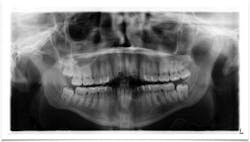

Figure 1: A view of the patient’s mass

Clinical assessment revealed a tissue-colored raised fluctuant mass on the left side of the lingual frenum, in the area of the submandibular gland duct. There was a slight tenderness to palpation with some firmness to the lesion overall. The mass measured approximately 4 mm by 5 mm in length (figures 1 and 2).

Figure 2: A view of the patient’s mass